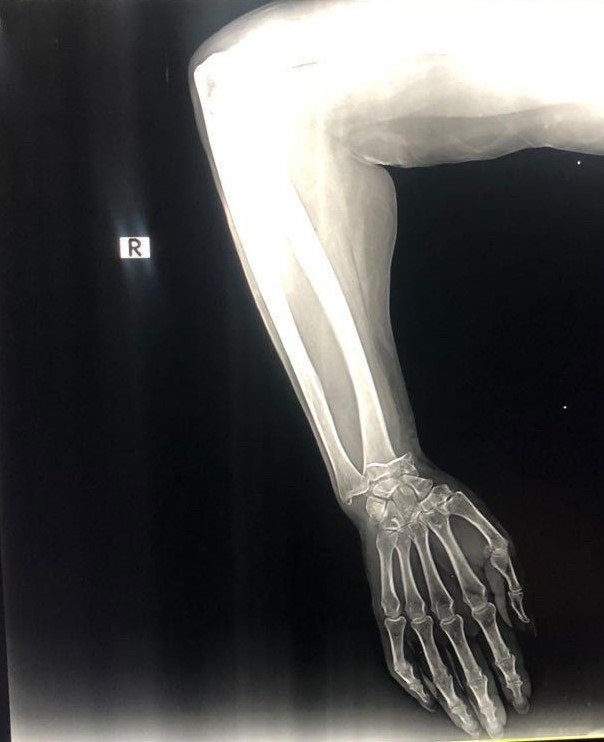

Olay, 4 Ağustos Cuma günü Kemer ilçesi Aslan Bucak Mahallesi Cuma pazarında yaşandı. Savaştan kaçıp Antalya'ya yerleşen Olena Buletsa (61), burada Şeyhmus Doğan ile yakın bir tarihte evlenen kızı Kateryna Buletsa'la (32) pazar alışverişine çıktı. Kızıyla birlikte yürüdüğü sırada dengesini kaybedip yere düşen Olena Buletsa'nın bileği kırıldı. Çevredekilerin durumu 112 Acil Çağrı Merkezine bildirmesi üzerine Buletsa ambulansla Özel Kemer Yaşam Hastanesine götürüldü. Burada iddiaya göre, sadece röntgen ve alçıya bin 680 dolar (günün kuruyla 44 bin 555 TL) fatura kesildi. Buletsa ve kızı bu parayı ödeyip evlerine döndü. Faturayı gören damadı Şeyhmus Doğan hastaneye gidip faturaya hastane çalışanları ve yetkililerine tepki gösterip itiraz etti. Olaydan bir gün sonrası ise 850 dolar geri yatırıldı. Hala olayın şokunda olan aile, paranın bir bölümünün geri yatırılmasına rağmen 800 doları fazla bulduklarını savundu.

"Cuma günü annemle çarşıya gittik. Sebzelerin yanında çok su vardı. Annem kaydı ve düştü. İnsanlar yardım etti, ambulans çağırdı. Ambulans geldiğinde sigorta olup olmadığını sordular. Ne yazık ki yoktu. Ukrayna'da bir savaş var. Şimdi yaşamak zor. Hangi hastaneye götürüldüğümüzü bilmiyordum. Orada doktorlar tıbbi bakım sağlamaya başladı. Ücretsiz olmadığını söylediler. Başka bir kliniğe gidelim dedim. Doktor "Türkiye'nin her yerinde pahalı" dedi. Röntgen çekildi. Cerrah kolu düzeltti ve bir alçı uyguladı. Bin 650 dolarlık bir fatura çıkardılar. Sonra acilen ameliyat gerektiğini söylediler."

Şeyhmus Doğan, "Hastaneye geldiklerinde sadece bir röntgen ve bu alçıyı yapıyorlar. Yatış yok, bıçak yok, ameliyat yok ve bin 650 dolar fiyat çıkıyor. Eşim devlet hastanesine gitmek istiyor, orası daha fazla para alır diyerek onu bu parayı ödemeye zorluyorlar. 44 bin 500 TL ödediler, 10 adet sargı bezi ve transfer. Ertesi gün ben gittim ve itiraz ettim. Polis çağırmamamı istediler. 850 dolarını geri yatırdılar. Kalan 800 dolar. Yine de bu alçıya 800 dolar verilir mi? Bu insanlar savaştan kaçtı, ben asgari ücretle çalışan birisiyim. Büyüklerimizin sesimizi duymasını istiyorum" diye konuştu.